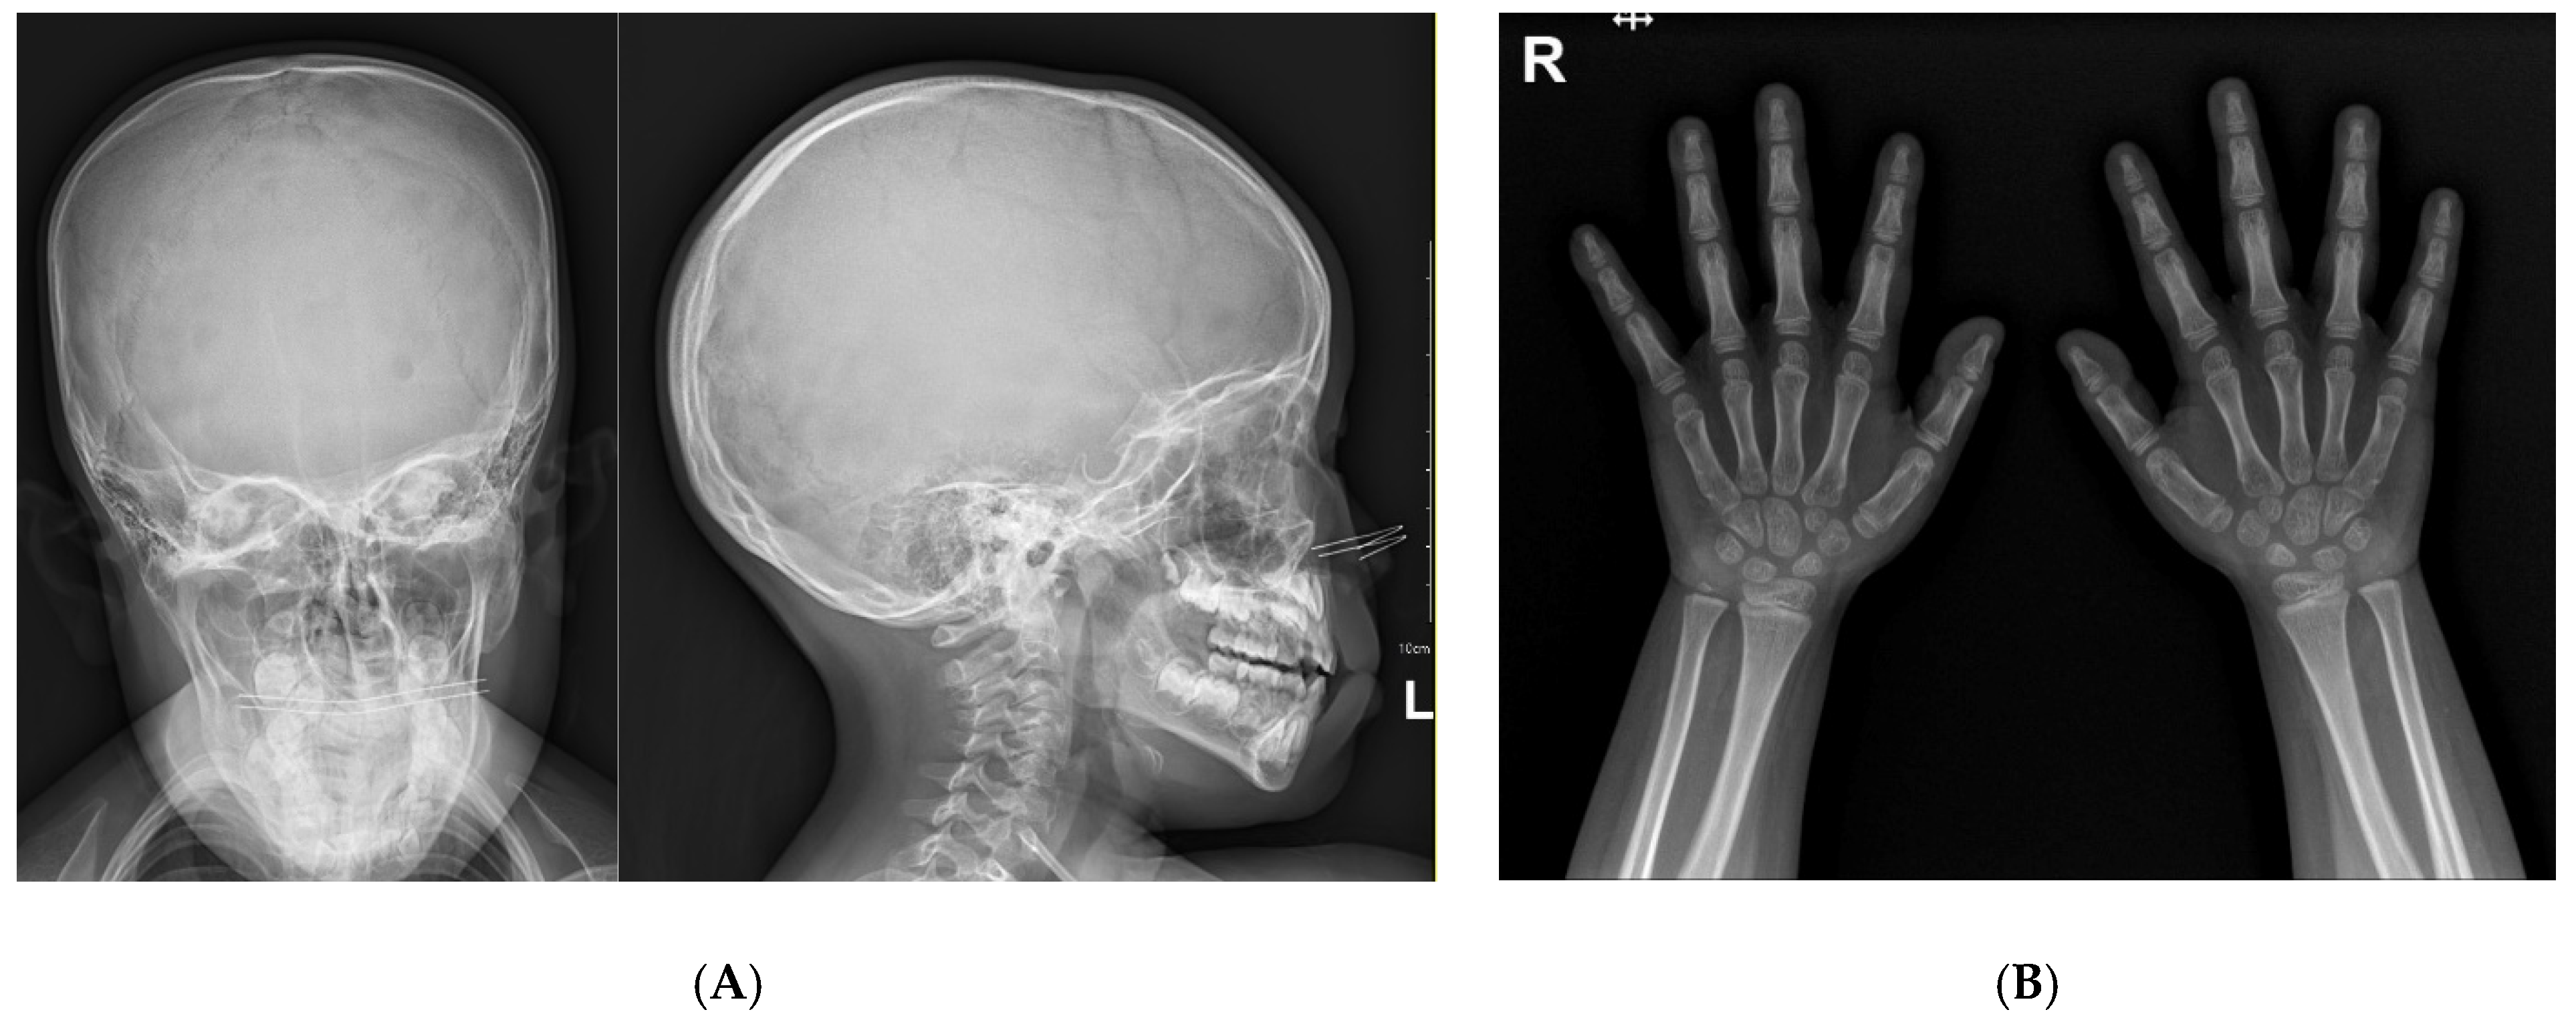

A 4-year-and-7-month-old girl presented with severe short stature below the 3rd percentile. She was born at 40 weeks of gestation with a birth weight of 2.9 kg (standard deviation score (SDS) = −0.75). Her perinatal and neonatal histories were unremarkable. Her parents are non-consanguineous, and her father had no underlying disease. Her mother had previously been under medical therapy for micro-pituitary adenoma. The patient had a healthy 9-month-old brother. No family members had any have current medical problems. On physical examination, her height was 91.1 cm (SDS −3.92), and weight was 15.5 kg (SDS −1.15). Her body mass index was 18.7 kg/m2 (SDS 2.05) as normal nutritional status. There were no conspicuous dysmorphic features on her face (Figure 1). Wide thumbs and great toes were observed on both sides (Figure 1) when compared with the other digits. Brachydactyly and syndactyly were not observed in the upper and lower limbs. We also confirmed closure of suture line, anterior and posterior fontanelle in x-ray of her skull series (Figure 2A). At the time of admission, bone age was advanced and measured approximately 7 years according to the Greulich and Pyle atlas (Figure 2B). There were no abnormal findings including serum electrolytes and insulin-like growth factor-binding protein 3 (IGF-BP3) level other than a decrease in the IGF-1 level (108.24 ng/mL, between the 25th and 50th percentiles) and an increase in the prolactin level (27.26 ng/mL, normal range 3.0–18.8 ng/mL) in the initial laboratory tests. Because of the elevated initial prolactin level and her family history, an MRI was performed before confirmation of the pituitary stimulation test results. An arachnoid cyst with a size of 3.5 × 2.6 cm was found in the left middle cranial fossa with magnetic resonance imaging (MRI) of the sella. There were no abnormal lesions in the sellar or suprasellar regions.

Figure 2.

Plain radiography (A) Anteroposterior and lateral of skull series. (B) Both hand X-rays at chronological age of 4 years and 7 months.